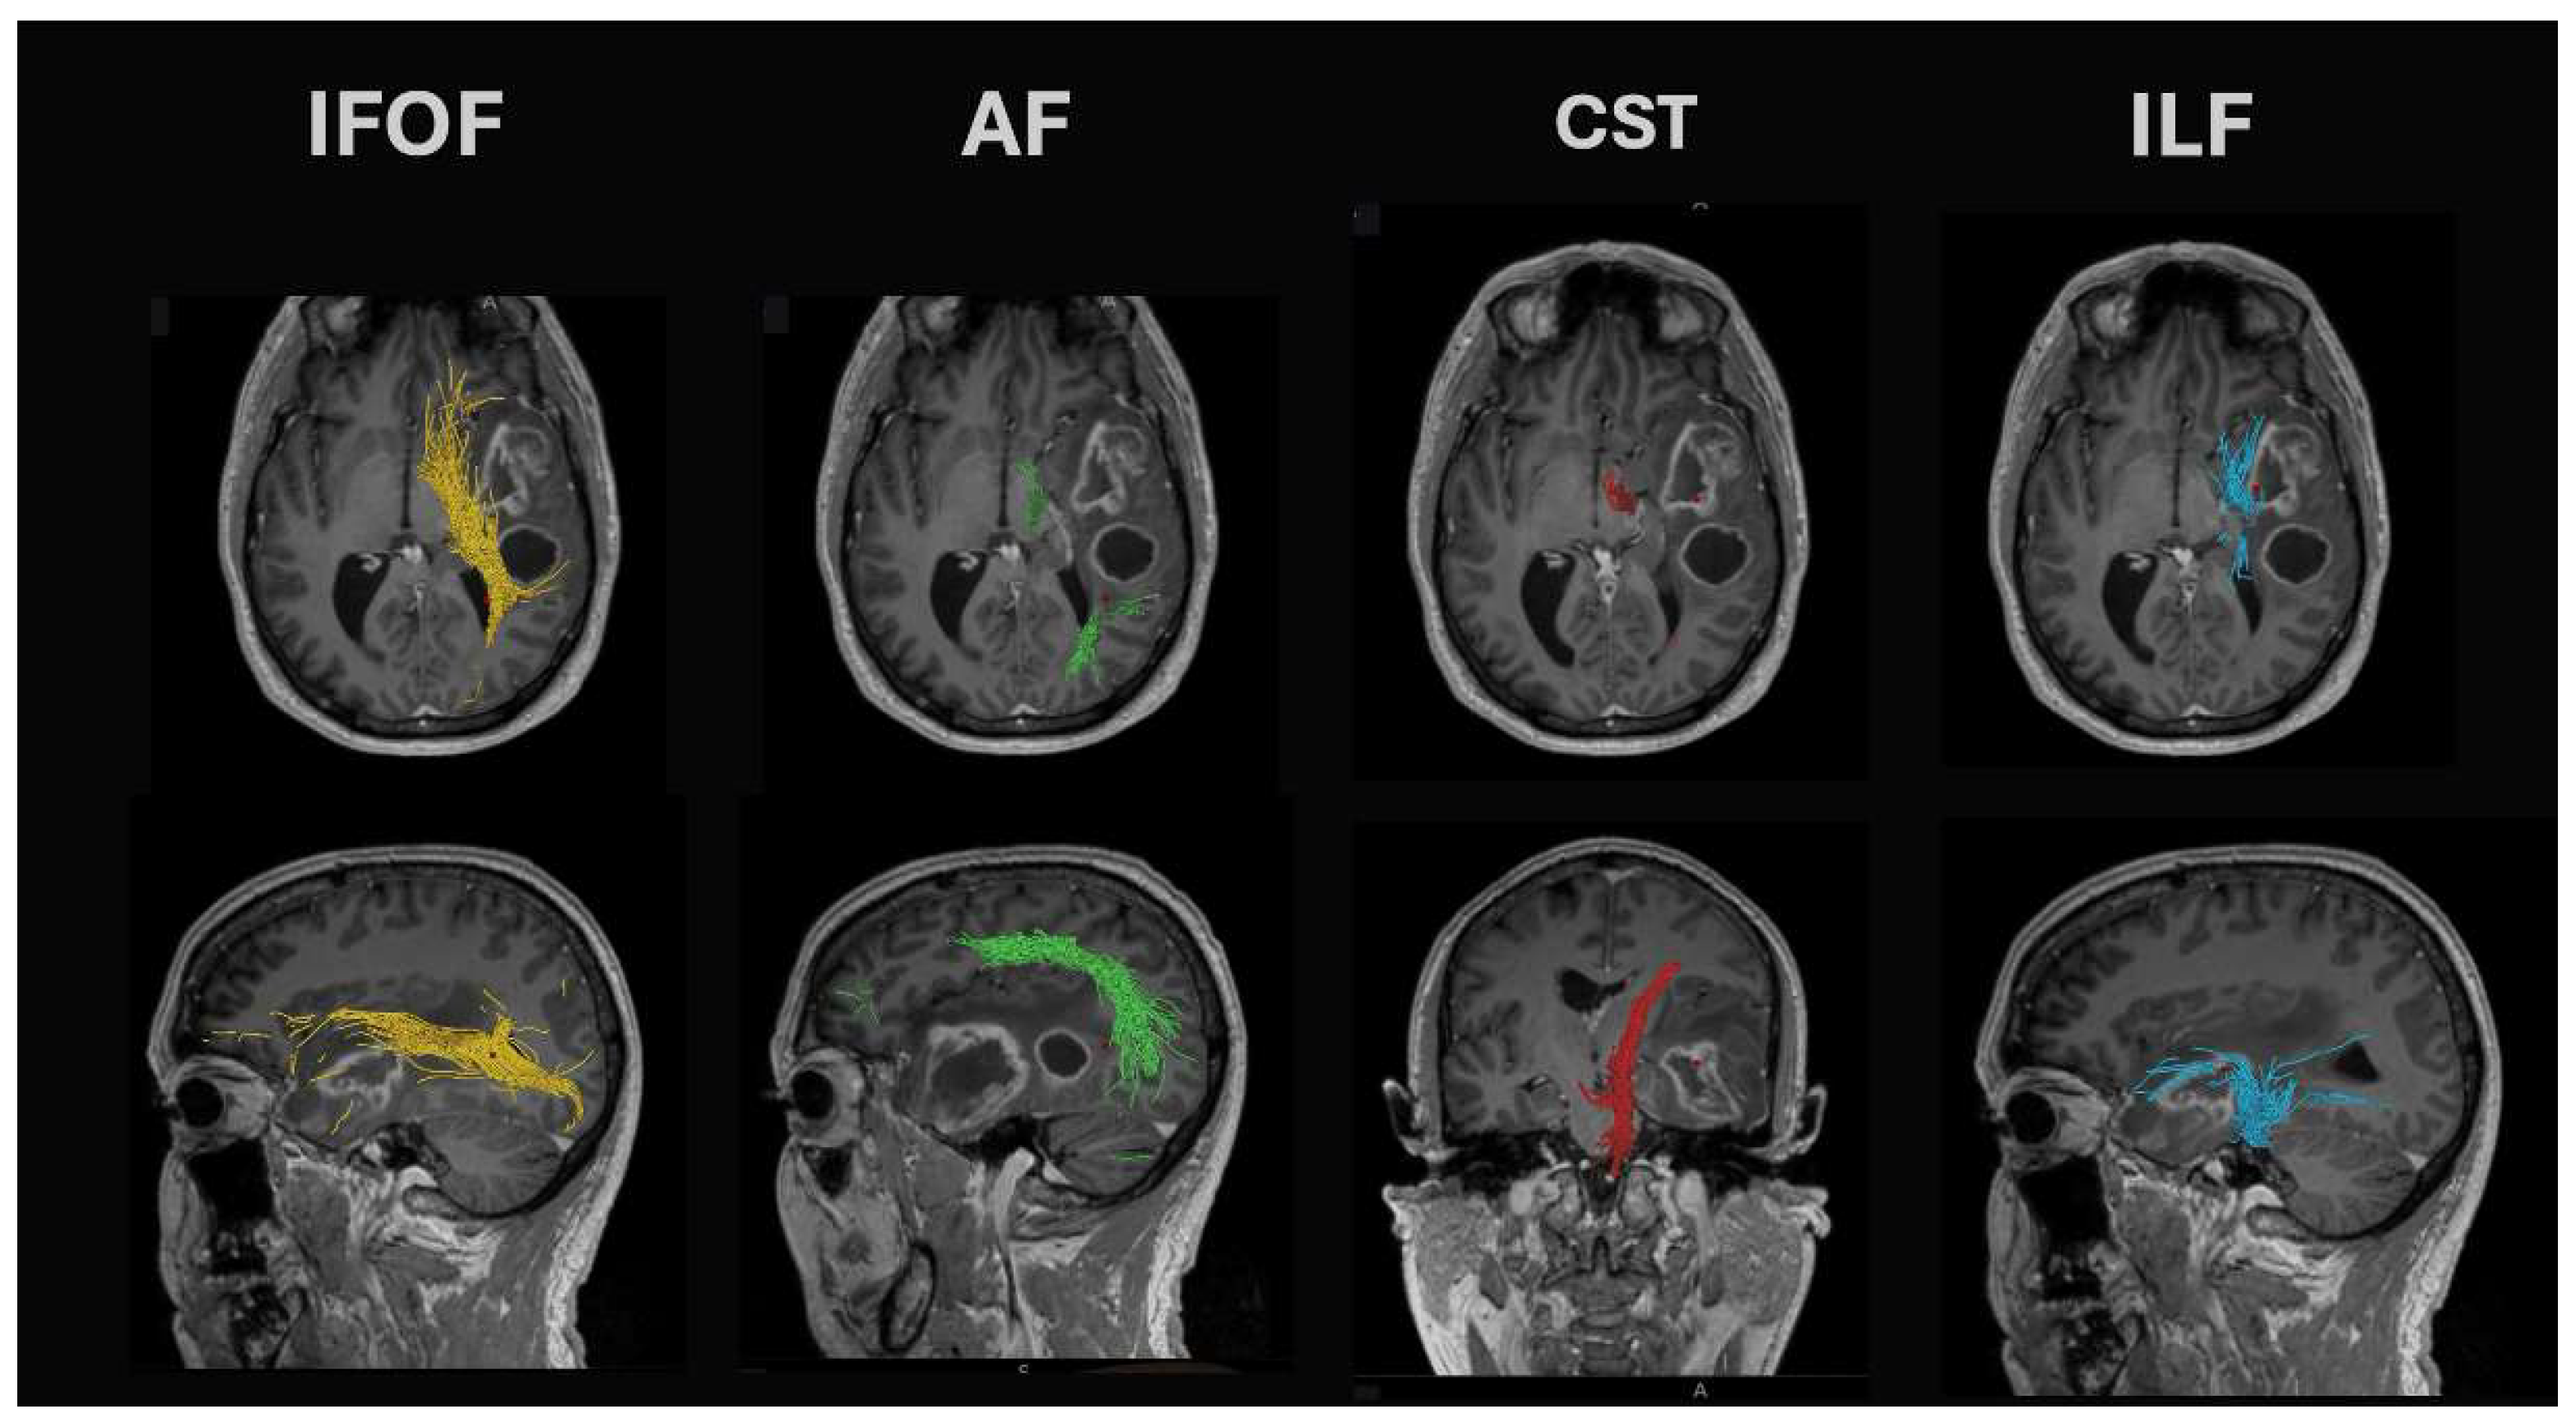

- Arcuate fasciculus: This tract is found in the peri-insular white matter in the circular sulcus of the insula. It links the superior temporal gyrus with the dorsolateral prefrontal and premotor cortices and is found together with the lateral SLF and inferior fronto-occipital fasciculus (IFOF). Lesions of the arcuate fasciculus lead to phonemic paraphasias, repetitions, and non-fluent ‘expressive’ aphasia.

- Superior longitudinal fasciculus (SLF): The temporoparietal branch connects the temporal lobe (posterior inferior, middle, and some superior temporal gyrus) with the parietal cortex (angular and supramarginal gyri). White matter dissection or standard DTI tractography methods cannot separate it from the arcuate fasciculus. Damage leads to fluent aphasia.

- Inferior longitudinal fasciculus (ILF): Connects the inferior temporal gyrus and runs posteriorly to the superior and middle occipital gyri. It runs between the optic radiation (found more medial) and the more lateral SLF. Seed points for DTI tractography are best seen on coronal views at the level of the middle/inferior temporal gyri. It demonstrates marked intersubject variability in cortical terminations. Damage can lead to problems with reading (alexia).

- Inferior fronto-occipital fasciculus (IFOF): These fibers pass from the frontal opercular cortex through the temporal stem to run on the roof of the temporal horn back to the occipital cortex. Damage leads to (visual) semantic deficits during naming tasks.